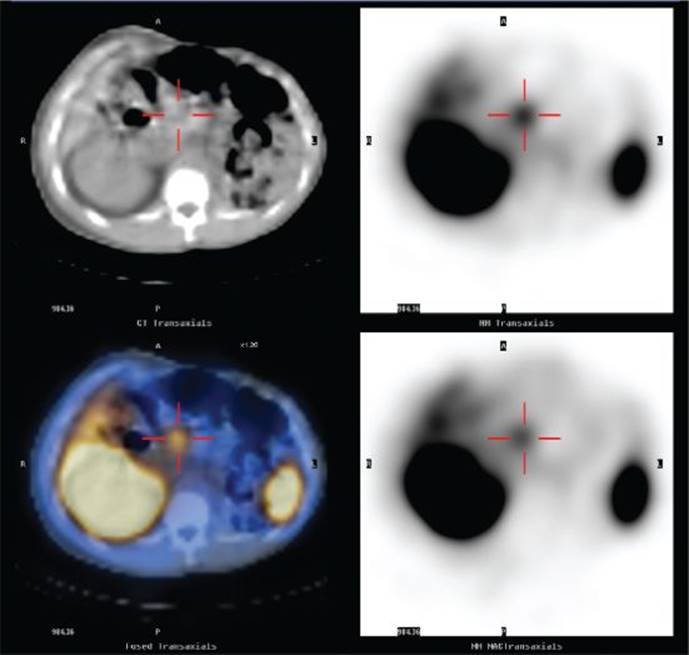

We then obtained a somatostatin receptor scintigraphy (SRS, also called octreoscan) that revealed focal, intense tracer uptake in the region of the head of the pancreas corresponding to the 3-cm lesion seen on CT scan (Figure 2).In addition, SRS also demonstrated a 1-cm tumor in the neck of the pancreas on the anterior wall, a third 8-mm tumor in the inferior portion of the head of the pancreas abutting the duodenum, and no scintigraphic evidence of distant metastases. The additional findings seen on SRS demonstrate the increased sensitivity of this modality over CT. SRS has a sensitivity that surpasses all other imaging modalities combined, and in the setting of ZES has an overall sensitivity of about 90%, specificity of 100%, and positive predictive value near 100%. Nevertheless, the sensitivity of SRS is still limited when interrogating for very small tumors. The sensitivity of SRS for tumors >2.2 cm is 96%, for tumors 1.1 to 2.2 cm is 64%, but for tumors <1.1 cm is only 30%. Because duodenal gastrinomas are usually subcentimeter in size, SRS fails to detect about 50% of these tumors.

FIGURE 2 • Octreoscan demonstrating focal intense tracer uptake in the pancreatic head region corresponding to the 3-cm hypervascular lesion seen on CT.